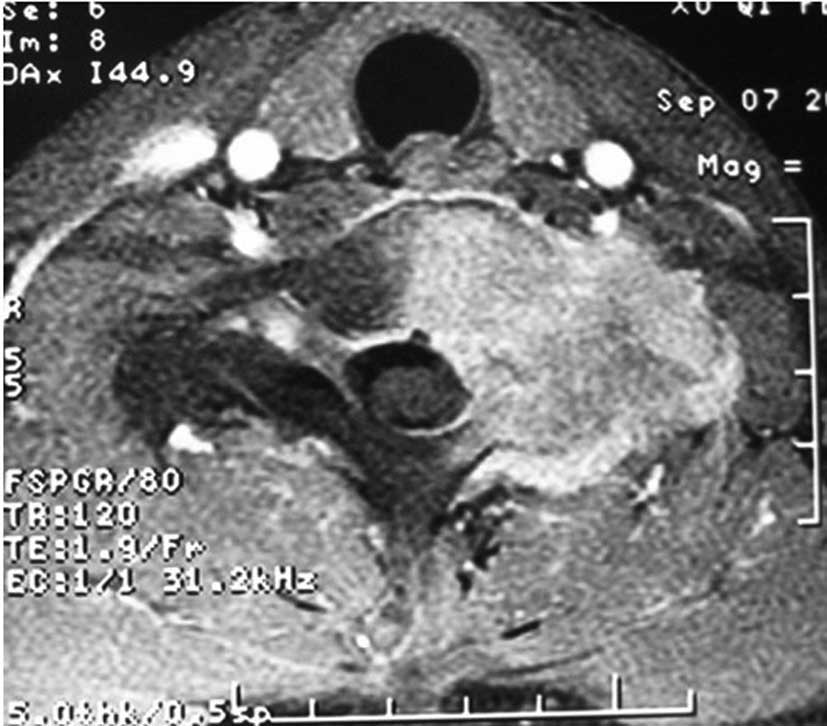

Primary dumbbell-shaped Ewing's sarcoma of the cervical vertebra in adults: Four case reports and literature review

Ewing's sarcoma is the second most common malignant bone tumor in children and adolescents. The 4 cases described in this study were diagnosed with dumbbell-shaped intraspinal and extraspinal Ewing's sarcomas. The incidence of dumbbell-shaped tumors of this type in the spine is 17.5%. These tumors are often misdiagnosed as neurogenic tumors (schwannoma, neurofibromatosis) or giant cell tumors based on imaging. Radiculopathy is more common than spinal cord compression in Ewing's sarcoma. Preoperative biopsy is strongly recommended. As soon as Ewing's sarcoma is diagnosed by pathology, the treatment should begin with 2-3 cycles of neoadjuvant chemotherapy. Anterior-posterior and posterolateral approaches are both recommended for exposing this tumor. Following surgery, chemotherapy is critical to lessen the rate of recurrence and metastasis and to prolong the survival time. However, radiotherapy should be used with caution, as the spinal cord is sensitive to radiation; local irradiation is suggested. The tumor is difficult to remove en bloc in the cervical spine. It has a high rate of recurrence and metastasis. Therefore, the prognosis of Ewing's sarcoma in the cervical region is poorer compared to that in the thoracic and lumbosacral regions.